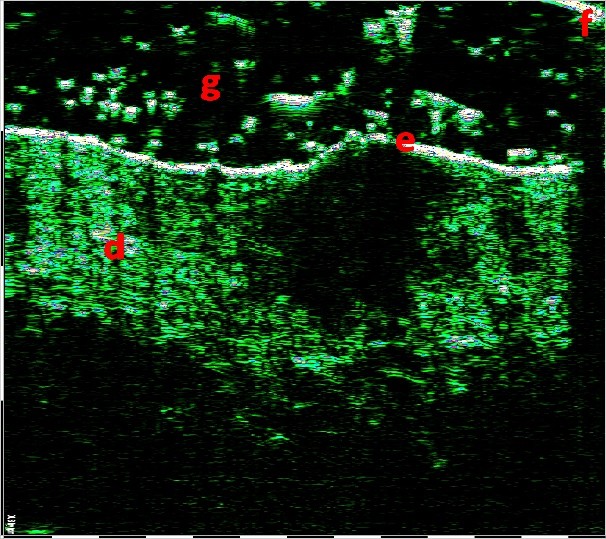

2.9mm depth , 7.1mm width

Οζώδες Βασικοκυτταρικό Καρκίνωμα. Σάρωση με υπέρηχο υψηλής συχνότητα που δείχνει τις διαστάσεις του όγκου και Βιντεοδερματοσκόπηση.

Η σάρωση υψηλής συχνότητας με τη χρήση αισθητήρων 22 και 75 MHz, επιτρέπει τη χρήση απλών κριτηρίων κακοήθειας για τη διάγνωση όγκων του δέρματος με υπερηχογραφικές ενδείξεις. Τα πιο έντονα κακοήθη χαρακτηριστικά είναι: σχηματισμός με τάση σταθερής ανάπτυξης, ανώμαλα περιθώρια και κατακόρυφος προσανατολισμός ανάπτυξης του όγκου, ο οποίος αναπτύσσεται σε βάθος και έχει ακανόνιστη θολή ετερογένεια, ενώ ταυτόχρονα η αγγείωση και η μικροκυκλοφορία ενισχύονται κατά την απεικόνιση Doppler.

Η βάση της επιτυχημένα επιλεγμένης τακτικής για τη θεραπεία του BCC είναι η σωστή αξιολόγηση της κλινικής του μορφής και της μορφολογίας του. Ο υπέρηχος υψηλής συχνότητας καθιστά δυνατή τη διαφοροποίηση των τύπων BCC: επιφανειακά, οζώδη, σκληροδερμικά και μικροοζώδη.

Τα επιφανειακά BCC στις υπερηχογραφικές σαρώσεις έχουν οριζόντια επιμήκη περιγράμματα με σαφή οριοθέτηση από το υποκείμενο χόριο με υποηχογενή δομή, ενώ τα οζώδη BCC χαρακτηρίζονται από στρογγυλά ή οβάλ περιγράμματα με διάχυτη υπο-ετεροηχογενή δομή και είναι επίσης σαφώς οριοθετημένα από τους περιβάλλοντες ιστούς. Συχνά οι κουκκίδες που μοιάζουν με εγκλείσματα εμφανίζονται στο κέντρο του όγκου και στην περιφέρεια.

Τα σκληροδερμικά BCC απεικονίζονται ως υποηχογενείς σχηματισμοί με ανομοιόμορφα περιγράμματα, που διεισδύουν βαθιά στο χόριο, με κυματιστά ασαφή όρια.